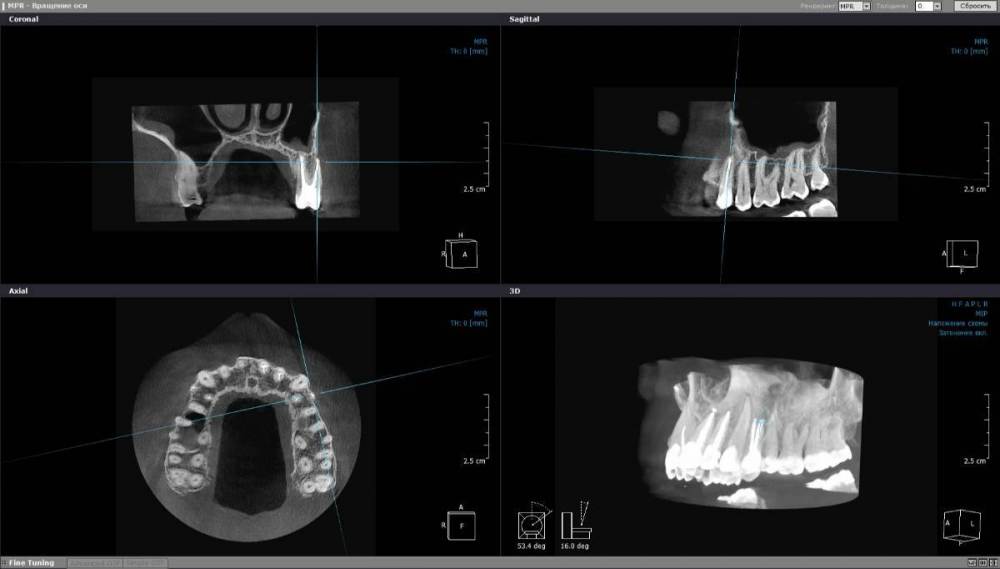

alexx123 Опубликовано 23 мая, 2023 Поделиться Опубликовано 23 мая, 2023 (изменено) Здравствуйте. В прошлом году лечил зуб 24-й зуб с периоститом. Сначала без микроскопа, после чего случился рецидив периостита. Потом перелечили под микроскопом. Спустя некоторое время появились разные ощущения в области корня зуба (покалывание, легкое жжение и т.п.). Стоматолог ничего не увидел на КТ. Позже начала течь прозрачная слизь в носоглотку и из носа. Ее позже стало закладывать нос. С походом к врачу к сожалению затянул. С недавнего времени симптоматика значительно ухудшилась: выделения стали белыми и густыми. Нос с левой стороны постоянно заложен. Сегодня ездил к ЛОРу. Лор направил к стоматологу. Завтра еду к стоматологу. Думаю удалить 24-й зуб. Посмотрите пожалуйста в нем ли причина? КТ верхней челюсти прикладываю. https://cloud.mail.ru/public/784w/BU8Ui7YZg Предыдущая КТ до начала лечения зуба: https://cloud.mail.ru/public/Zfhf/NcjmRfbej Изменено 23 мая, 2023 пользователем alexx123 Ссылка на комментарий

wladdX Опубликовано 23 мая, 2023 Поделиться Опубликовано 23 мая, 2023 Ничего криминального не увидел. К\каналы зуба 24 полечены достойно. Может коллеги увидят иначе. 1 Ссылка на комментарий

Doc Опубликовано 24 мая, 2023 Поделиться Опубликовано 24 мая, 2023 Судя по снимку корень не имеет выхода в гайморову, пролечен нормально и вряд ли влияет на процессы в пазухе. Ссылка на комментарий